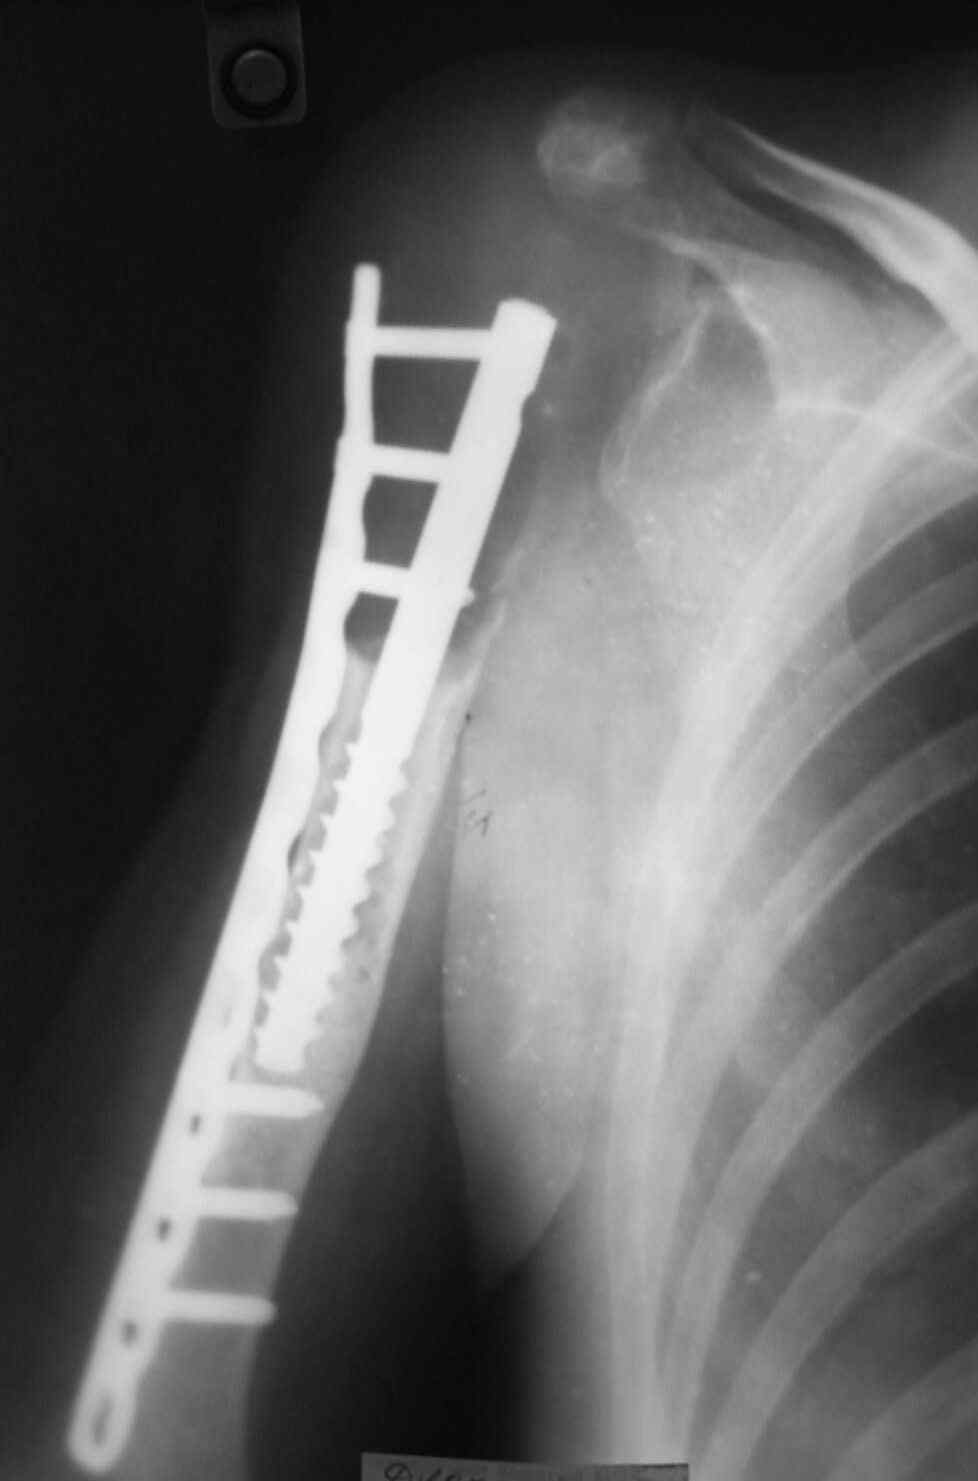

Выполнена операция- малоинвазивно проведена LCP пластина в образованный канал над

головкой протеза, фиксирована к протезу и дистально к плечевой кости, на зоной резорбции

трепонирована кость, удалена соединительно-тканная оболочка, полость заполнена

chronOS. П/о период без осложнений, клиника нестабильности купирована. Прошло 2 года по

телефону сообщила, что у нее все хорошо, продолжает жить счастливой жизнью сельской

труженицы